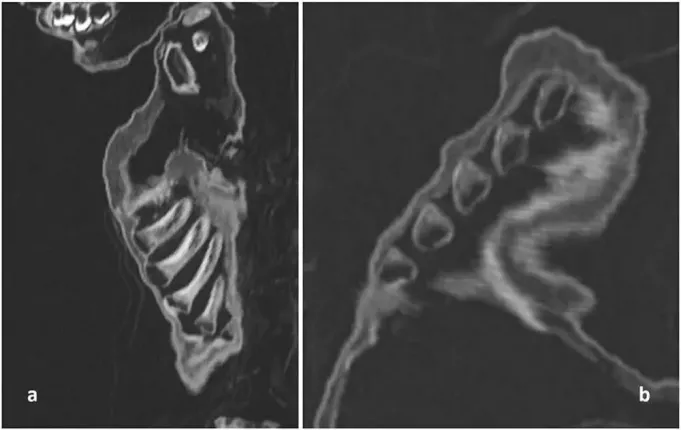

Bilim insanları, diş patlamasını, vücudunun kemiklerinin oluşumunu, uzunluğunu inceleyerek, çocuğun yaklaşık 1 yaşında olduğunu tahmin edebildiler. Kemik incelemesinde, bozuk kaburgalarında raşitik tespih belirtileri bulan araştırmacılar, D ve C vitamini eksikliklerinden kaynaklı hastalık olduğunu belirttiler.

ZATÜRREDEN ÖLMÜŞAkciğerlerdeki iltihaplanma kanıtlarına bakılırsa, çocuk zatürreden ölmüş gibi görünüyor. Rickets'in çocukları zatürreye karşı daha savunmasız hale getirdiği biliniyor. Bu, ne yazık ki çocuğun yetersiz beslenmesinin yanı sıra bu durumun da onun zamansız ölümüne yol açmış olabileceğini düşündürüyor.